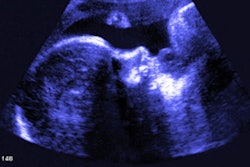

Currently underway in Guatemala, India, Peru, and Rwanda, the HAPIN study is a randomized controlled trial to assess how using liquefied petroleum gas stoves instead of customary cooking practices affects air pollution, child health, and adult chronic disease, according to MedaPhor. As part of the trial, 3,200 pregnant women are being monitored with ultrasound to assess gestational age and fetal development. MedaPhor's sonographer panel and ScanNav artificial intelligence-based image inspection algorithms will be responsible for ensuring that these images are of the highest quality, the company said.